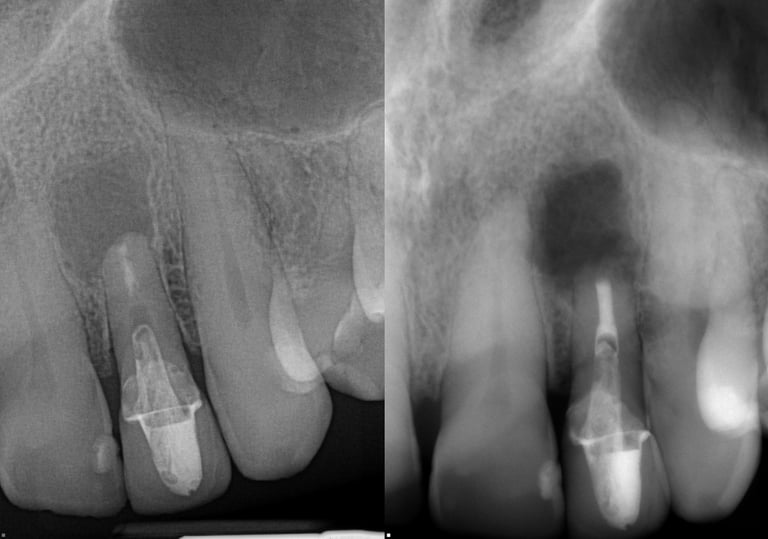

Gallery 2: Retreatment Cases

Retreatment Root Canal Cases with preoperative and postoperative radiographs.

#10 ReTx (original RCT poorly done)

#30 ReTx (original RCT had missed canal)

#14 ReTx (original RCT had missed 4th canal)

#19 ReTx (original had missed canal)